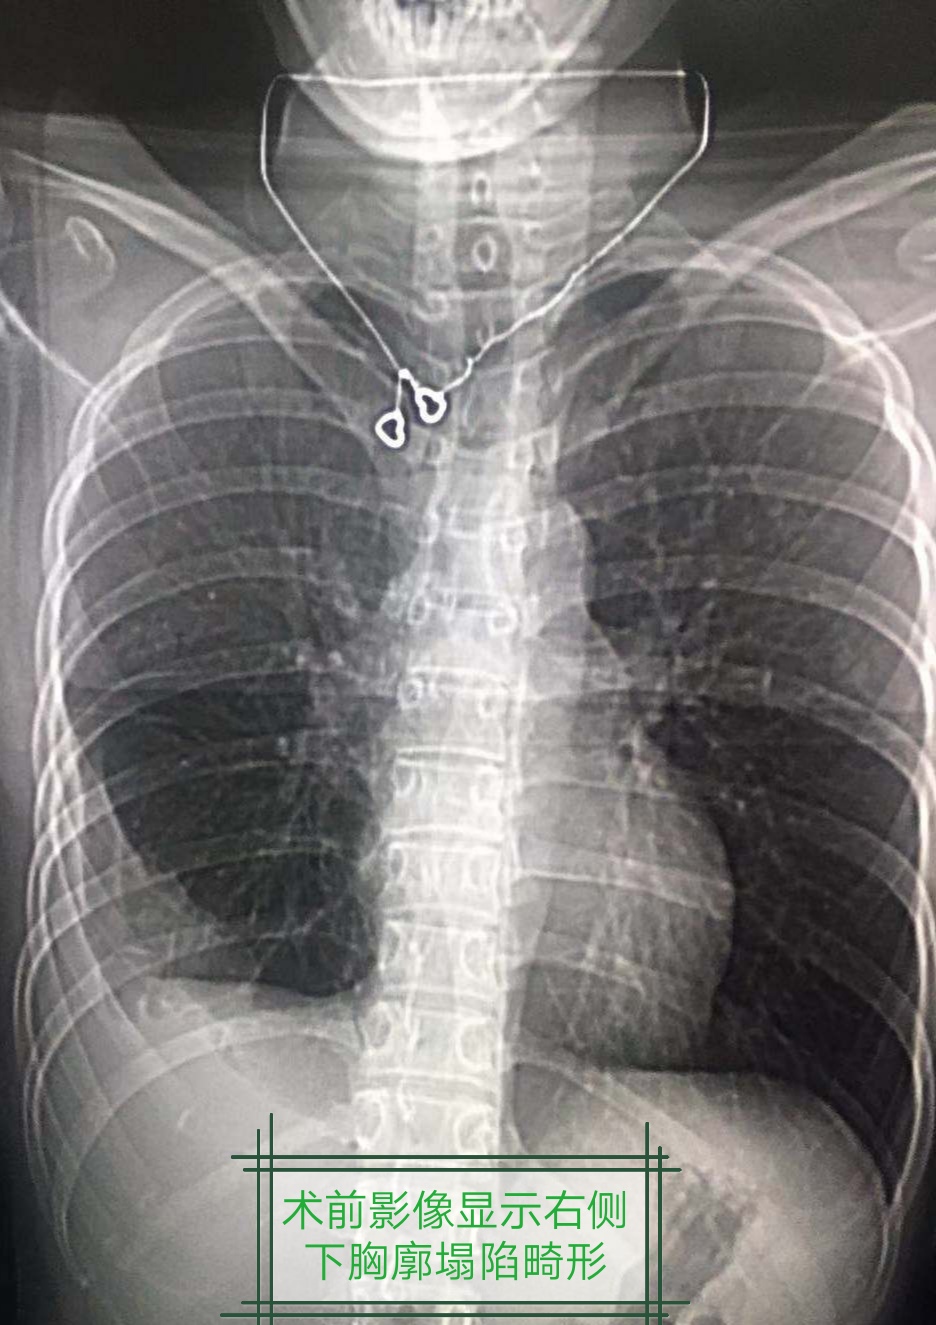

一位花季女孩不幸遭受慢性脓*摧胸**残,保守治疗右侧脓腔不能消灭,胸廓塌陷,开胸手术实在难以接受������

高兴的向我们汇报:手术前我深呼吸受限,胸部像带着紧箍咒一样,肩膀也是斜的,脊柱是弯的,手术后回家对时候家里人惊讶的发现,我的两肩一边高了,脊柱也直了!我现在是真轻松了!期待再次复查,继续给她惊喜……这就是现代科技进步给病人带来的实实在在的福利。